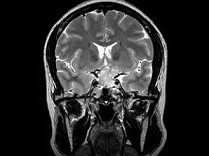

女,38岁,左侧视力下降伴头昏1个月余,根据所提供图像,最可能的诊断是()

女,38岁,左侧视力下降伴头昏1个月余,根据所提供图像,最可能的诊断是()

[单选题]女,38岁,左侧视力下降伴头昏1个月余,根据所提供图像,最可能的诊断是()A . 颅咽管瘤B . 垂体嫌色细胞腺瘤C . 视神经胶质瘤D . 软骨瘤E . 脑膜瘤